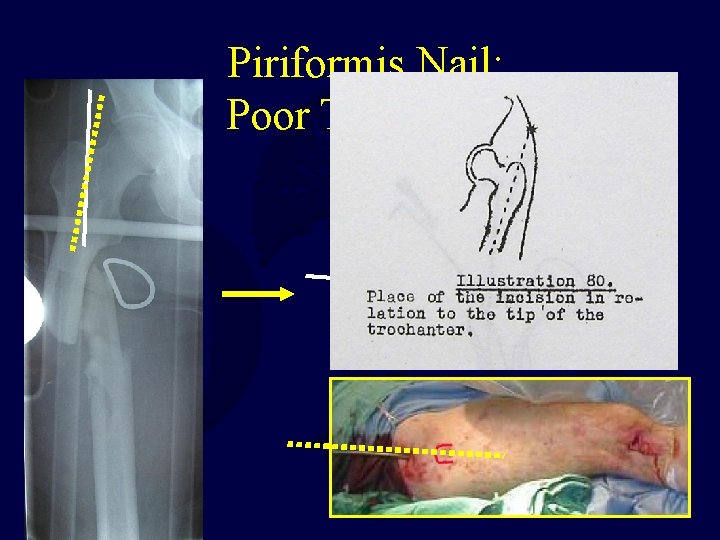

Piriformis Nail: Poor Technique

Piriformis Nail: Poor Technique